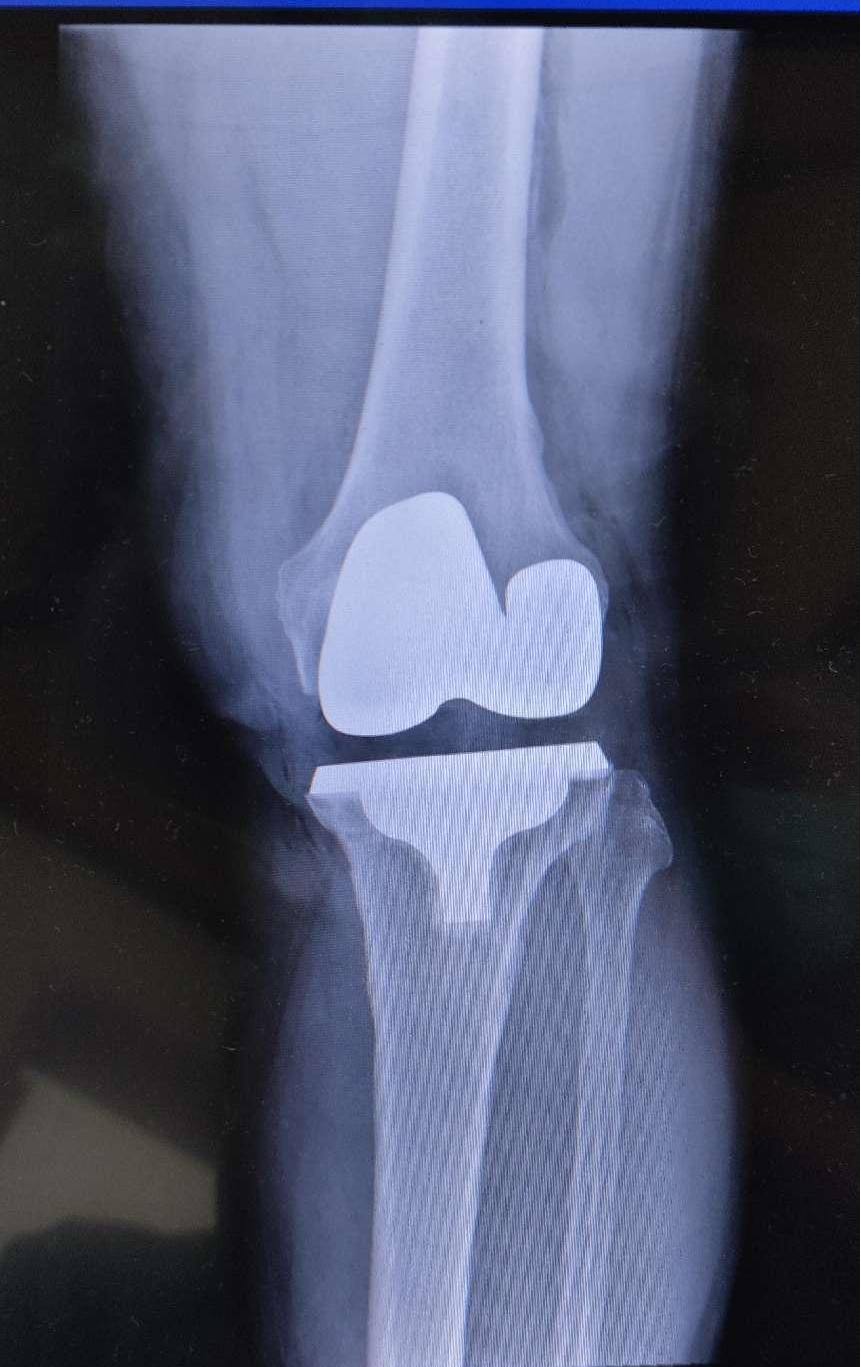

一、运动力线内轴式膝关节表面置换术。不同于国内普遍开展的传统的机械力线,运动力线手术更多地体现了病人优先的原则。术中充分尊重患者原有的膝关节力线和运动轨迹,并予以最大限度的复原,为患者取得了满意的效果。

二、机器人电磁导航辅助下人工膝关节置换术。在复杂病变的病例中,机器人电磁导航相较于术者手工测量,有着得天独厚的优势。它可以极大地提高术者对膝关节截骨的测量精度,减小手术当中的误差,从而避免了灾难性失误对术后患者膝关节功能造成的不良影响。同时,机器人导航为术者提供了极为精准的截骨角度,弥补了初学者经验不足的缺点。对该技术的学习使我对国内关节置换的发展方向有了更进一步的认识。